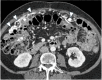

Management of peritoneal surface malignancies is currently entrusted to a multimodality approach. Computed tomography (CT) scan remains the first imaging method despite the limitations in identifying small implants in critical regions. Magnetic resonance imaging is usually recommended for its performance in small implants, mesentery, and small bowel assessment. Positron emission tomography/CT plays an important role only in pseudomyxoma peritonei. Thus, becoming aware of the imaging strengths and drawbacks and having a multimodality imaging approach might be the best option for the patients.